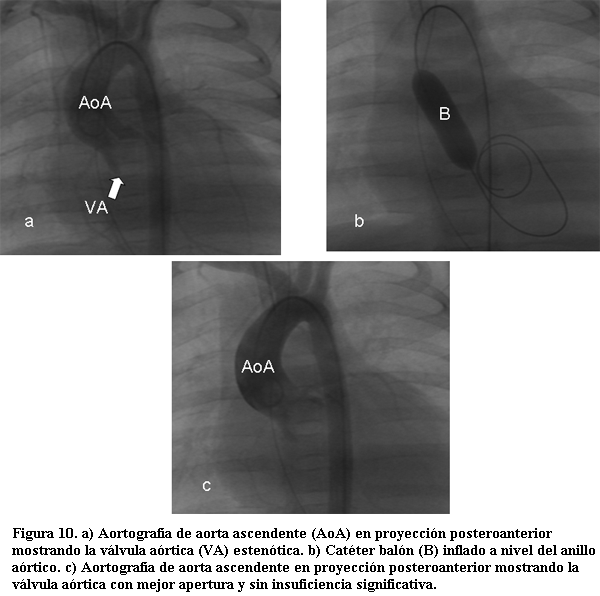

La valvuloplastia aórtica mediante catéter balón es siempre paliativa, y puede realizarse con dos fines:

1. Puramente paliativa en el marco de una cardiopatía congénita compleja, donde la desgravitación del ventrículo izquierdo puede lograr la compensación del paciente para llevar a cabo en mejores condiciones y con menor riesgo el plan terapéutico correspondiente.

2. Paliativo-curativa en casos de estenosis valvular aórtica aislada con buena anatomía de la válvula, donde este tratamiento puede ser eficaz inicialmente y lograr en buena parte de los casos un periodo prolongado libre de reintervenciones.

Las vías de acceso son la aórtica retrógrada o la vía anterógrada accediendo a la aurícula izquierda a través de un foramen oval permeable o por punción transeptal.

Para su realización se debe elegir un balón con un diámetro que no sobrepase el diámetro del anillo aórtico, para disminuir las posibilidades de aparición de la complicación más temida que es la insuficiencia aórtica.

Internacionalmente se está trabajando en la realización de la valvuloplastia aórtica en período prenatal, en casos de estenosis valvular aórtica crítica, para mejorar el desarrollo del ventrículo izquierdo, es un procedimiento que aún presenta una elevadísima morbimortalidad con resultados inciertos (figura 10) (60,61).